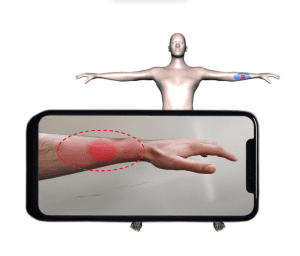

In Bereichen wie Verbrennungsmedizin, chronischem Wundmanagement oder Forensik spielt die Körperoberfläche eine zentrale Rolle. Deshalb erstellt das Forschungsteam virtuelle 3D-Avatare von Patient*innen, die reale Körper möglichst exakt abbilden. Damit lassen sich Wunden präzise lokalisieren, dokumentieren und im Zeitverlauf objektiv bewerten.

Übertragung einer Brandwunde von einem 2D Bild auf ein 3D Patient*innen-Modell. Die automatische Wundlokalisation und Anpassung des 3D Modells an die Körperform desder Patient*in ermöglicht eine objektivere Bestimmung der Wundgröße und Dokumentation des Heilungsverlaufs.

Verbrennungsklassifikation

Patient*innen mit Verbrennungswunden werden in der Notaufnahme initial behandelt. Mittels medizinischer Modellierungsmethoden wird ein virtuelles 3D-Körperoberflächenmodell anhand eines RGB-D-Scans an die Patient*innen angepasst. Die Verbrennungstiefe wird anhand von Bildanalysemethoden klassifiziert. Die Wunden (Ausdehnung und Tiefe) werden am Körperoberflächenmodell dokumentiert. Der zeitliche Verlauf der Wunde aufgrund der späteren Behandlung wird am Körperoberflächenmodell dokumentiert und kann so für die Verbesserung der Behandlung zukünftiger Patient*innen genutzt werden.